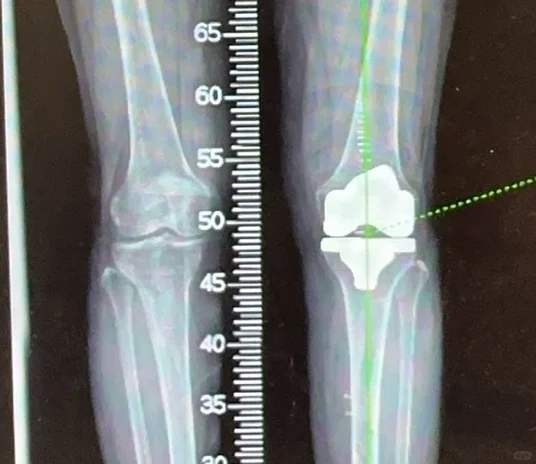

髋膝关节置换手术是二十世纪以来最成熟的手术,1小时的手术时间能够给患者带来关节的重生,从此告别让人无法忍受的疼痛,回归正常生活,老人上下楼梯爬山跳舞不是梦。

给大家看看我们的手术器械和术后影像,抡大锤的马医生在线回复您的疑问,点个关注,持续解答。